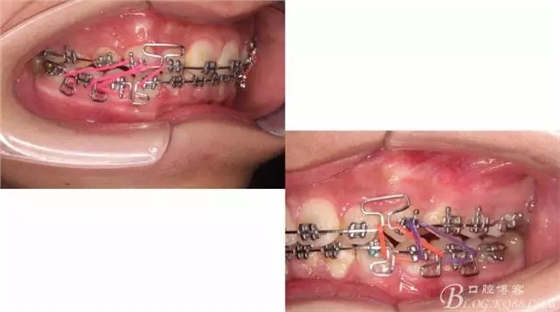

接下來盡管配合些雙側后牙對角牽引,咬合關系依,不盡人意。

下頜配合多曲方絲,三角牽引,調整咬合。

中線不齊,咋辦?繼續(xù)哄哄患者配合,2牽+斜牽。